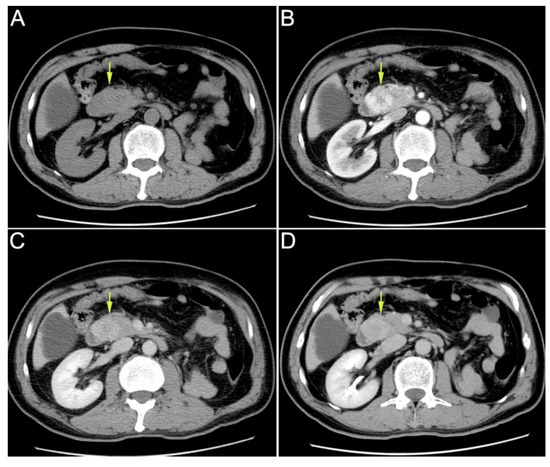

The duodenal papilla was plump with pulsatile bleeding by emergency duodenoscopy (A). The ampullary mass was observed by endoscopic ultrasonography, with a size of 22.7 × 28.2 mm (C). We diagnosed that the tumor had invaded the artery and the bleeding site was indistinct due to the persistent bleeding. Hemostasis was performed by using an endoscopic metal clip and the hemorrhage was partially relieved (B). However, due to the fragility of the tumor, complete hemostasis was difficult. Then, we tried to perform TAE in hemostasia. However, there were no obvious signs of contrast extravasation (D). After a Multi-Disciplinary Treatment (MDT), we decided to perform emergency pancreaticoduodenectomy, which was recommended by most experts on MDT. Intraoperatively, it was found that the tumor was located in the ampulla of vater and had invaded the pancreatic tissue. Modified Child anastomosis was performed after radical pancreaticoduodenectomy: gastrojejunostomy (Braun’s anastomosis), pancreaticojejunostomy (anastomosis of pancreatic duct with jejunal mucosa through a tent duct), and biliojejunostomy (end-to-side). He also underwent fenestration for a cyst in his right liver. The operation went well.